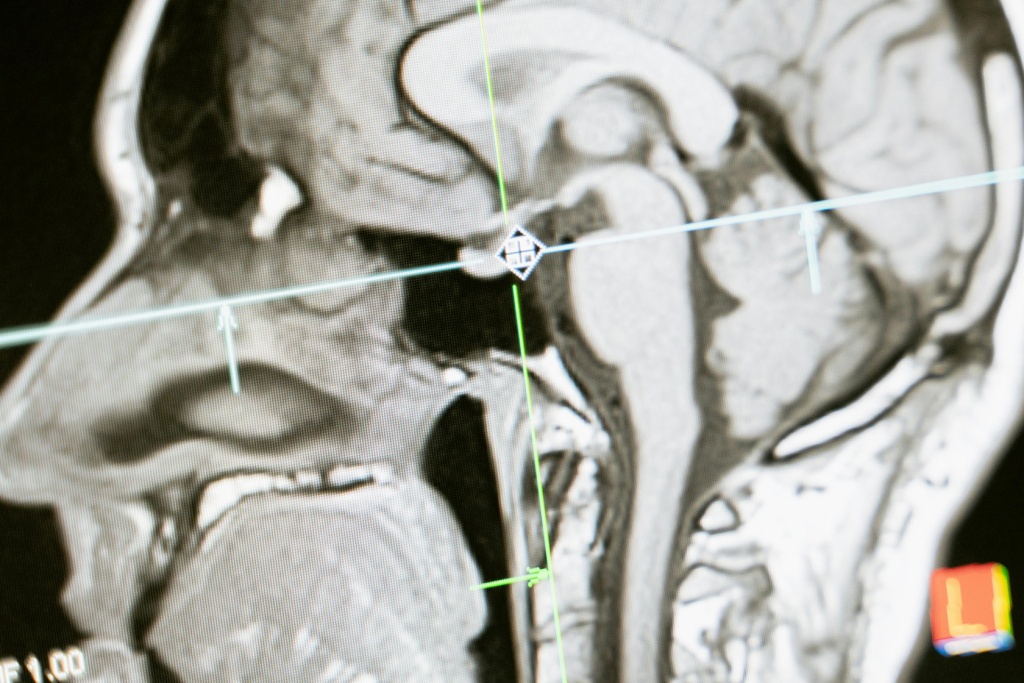

Предположим, у пациента обнаружили подозрительные изменения в тканях мозга на рентгеновских снимках. Для более точной диагностики врач назначает ему МРТ. Благодаря пониманию режимов МРТ, радиолог способен выбрать оптимальные параметры сканирования, что позволит получить высококачественные изображения мозговых структур с высоким разрешением. Это поможет точно определить характер и стадию заболевания и разработать наиболее эффективный план лечения для пациента.

Основная функция фМРТ заключается в том, чтобы позволить исследователям изучать активность мозга в реальном времени, что позволяет понять, какие участки мозга активируются при выполнении различных задач и функций. Этот метод широко используется в исследованиях мозговой активности, когнитивных функций, психических расстройств и нейрологических заболеваний.

В клинической практике фМРТ часто применяется для диагностики и мониторинга состояний, связанных с функционированием мозга, таких как эпилепсия, инсульты, шизофрения, депрессия и дисфункции речи. Также он может быть использован для планирования хирургических вмешательств, например, для определения местоположения функционально важных областей мозга перед операцией.